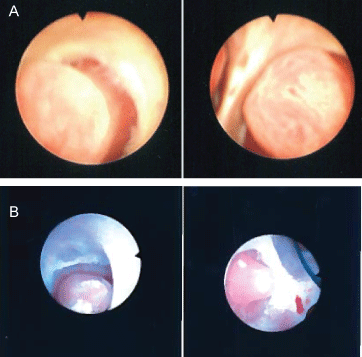

The patient underwent cystoscopy with bilateral retrograde pyelogram that revealed efflux of bloody urine from the left ureteral orifice, and filling defects in the left renal pelvic and lower pole calyx (Figure 1). The ureter was stented with a double J stent and subsequent ureteroscopy was performed. The patient was found to have renal papillae which were significantly hypertrophied and highly vascularized (Figure 2). The papilla of the lower pole calyx was hypertrophic to the point of protrusion into the renal pelvis. These hypertrophied lesions were biopsied and then ablated with a holmium laser. Pathology revealed benign fragments of renal medulla with tubular calcifications. MR angiogram performed one month later showed no vascular lesions or malformations. MR urogram showed prominent medullary pyramids in bilateral upper poles, consistent with renal papillary hypertrophy (Figure 3). The patient was followed without recurrence of hematuria for over 9 months.

Figure 2a: Hypertrophied papilla of the left mid pole and lower pole calyx. Case 1-EC.

Figure 2b: Hypertrophied papilla of the left upper pole calyx. Case 2-AS. View Figure 2

Patient underwent cystoscopy with retrograde pyelogram that revealed a filling defect in the upper pole calyx of the left kidney, but no lesion in the bladder or contralateral kidney (Figure 1b). A double J stent was placed with delayed ureteroscopy. On ureteroscopy, all the calyces of the left kidney were congested, enlarged, and demonstrated hypertrophic papilla (Figure 2b). Active oozing of blood was seen from the papillae in the upper pole calyx, which was ablated with a holmium laser. Patient was free of hematuria on follow-up for one month. She had recurrence of hematuria with MRI and MR urogram negative for pathology other than bilateral papillary hypertrophy. Patient's symptom of hematuria resolved and she is asymptomatic for 9 months.